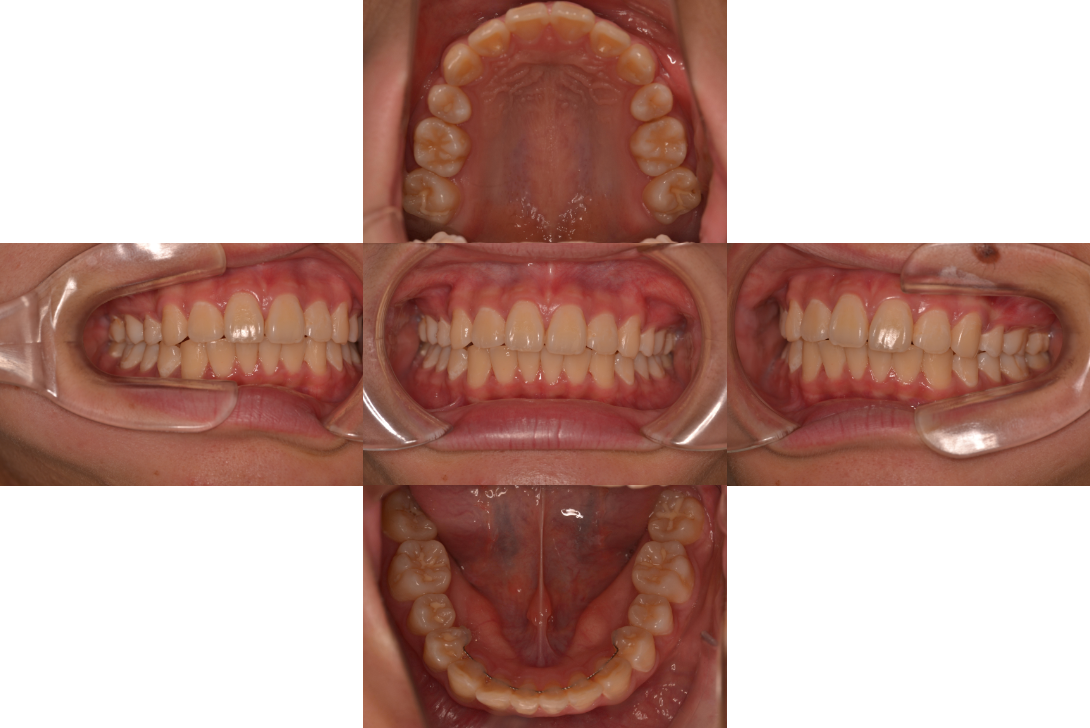

過蓋咬合を床矯正装置、下顎骨の前下方成長の促進で改善した症例

患者情報

11歳男性

主訴

咬み合わせを直したい

行った治療内容

床矯正装置、下顎骨の前下方成長の促進

治療のリスク

使用時間が短いと効果でない

治療期間

動的治療期間1年6か月

※ クリックして拡大することができます。